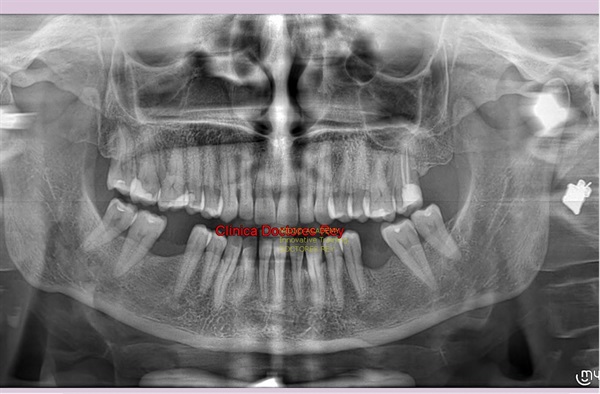

2-Implantes monobloque, en maxilar inferior. MIDI® TECHNIQUE® -US.

4x11,5. colocados con técnica ultarasónica MIDI®, hueso de calidad baja.

1- Implante de 9 mm de diámetro en maxilar superior post extracción + PRF. MIDI® TECHNIQUE®, no drill.

IMPLANTE EN MAXILAR SUPERIOR post extracción de diametro amplio 9 mm.

1- Implante de 9 mm de diámetro en maxilar superior post extracción + PRF. MIDI ®TECHNIQUE®, no drill.